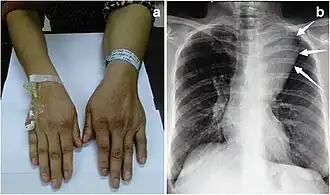

Angiolipoma mediastinal grande

O angiolipoma é um nódulo subcutâneo com estrutura vascular, com todas as outras características de um lipoma típico. Eles geralmente são dolorosos.[1]:624[2] Os angiolipomas se manifestam como múltiplos nódulos subcutâneos dolorosos, geralmente nos membros superiores. Podem ocorrer esporadicamente, com histórico familiar ou após trauma. Os angiolipomas podem ser vistos em tomografias computadorizadas e ressonâncias magnéticas, mas o diagnóstico é feito com base na histopatologia. A excisão total ou a lipoaspiração são usadas para tratar os angiolipomas. Eles são mais comuns em homens e geralmente aparecem na segunda e terceira décadas de vida.

O angiolipoma geralmente se manifesta como muitos nódulos subcutâneos dolorosos (solitários em apenas um terço dos pacientes), mais comumente originados nos membros superiores (dos quais o antebraço representa cerca de dois terços), no tronco e nos membros inferiores.[3][4] Essas lesões são bem definidas, geralmente medindo menos de 4 cm.[5]